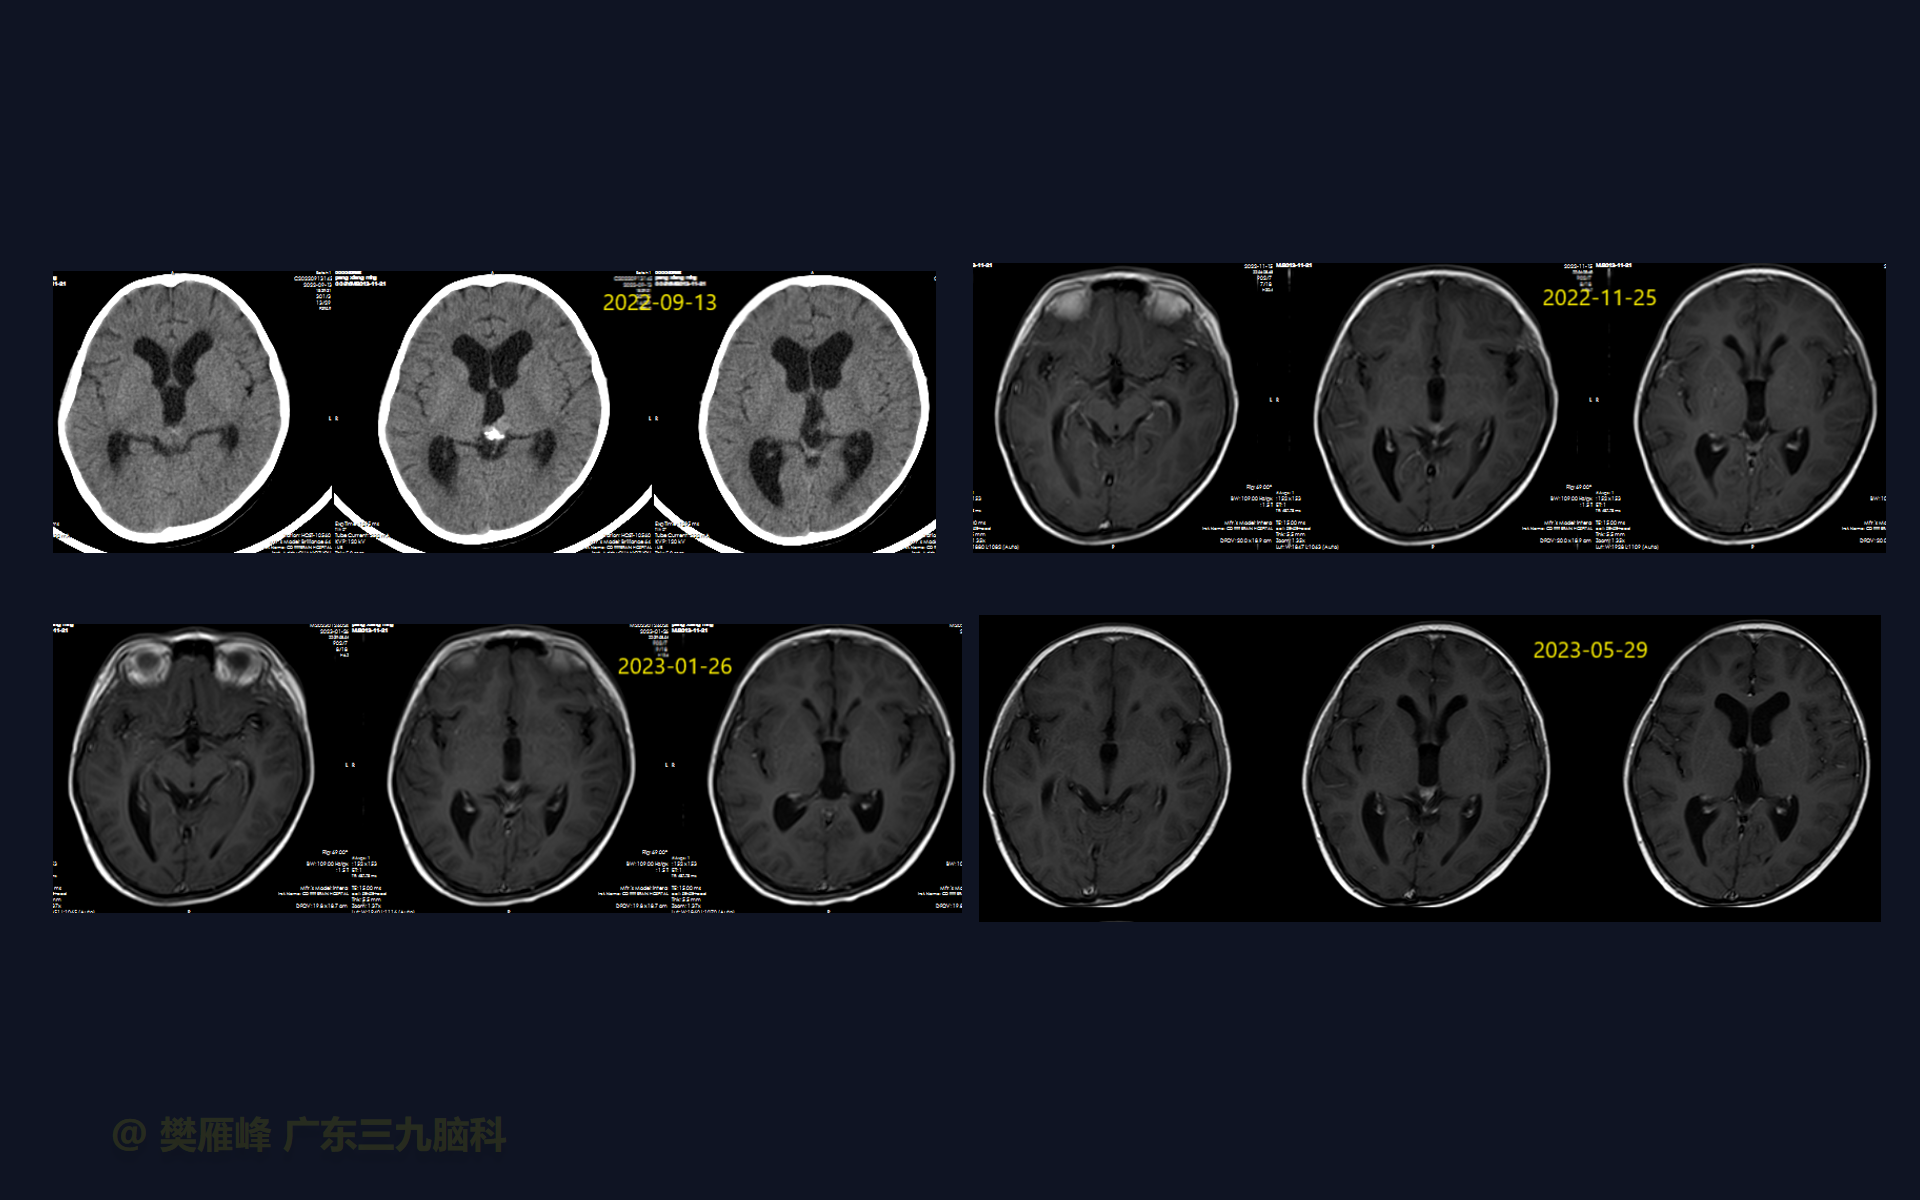

在这个二维手术视频中,展示了2例神经内镜下三脑室底造瘘+活检治疗三脑室后部肿瘤的方法。患者均为三脑室后部病变导致的梗阻性脑积水,病理结果1例为生殖细胞瘤,1例为淋巴瘤,在经过术后的放化疗病情均得到控制,生活质量满意。我们展示了安全的病变活检和第三脑室造瘘的技术要点,以最大限度减少术后继发脑积水和早期并发症。